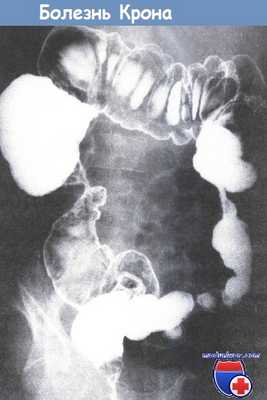

Болезнь Крона в форме колита: стриктуры и параректальные свищи